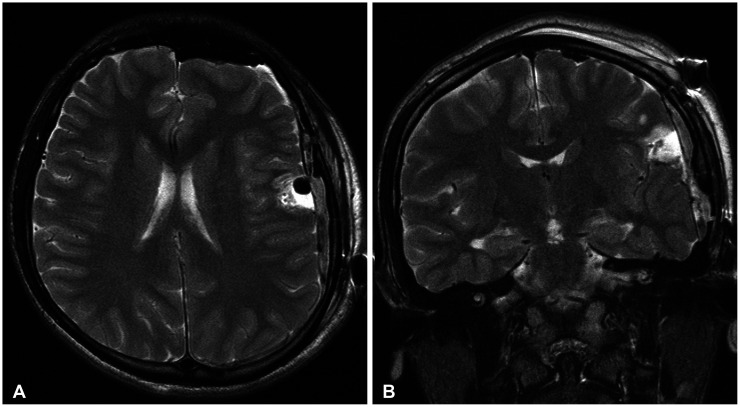

Angiocentric glioma (AG) is an extremely rare tumor that often develops in adolescents. Awake surgery for AG occurring in the eloquent area has not been reported to date. We report a case involving a right-handed 15-year-old boy with AG. He presented with a first-time generalized tonic-clonic seizure and was rushed to the local hospital. CT of the head indicated a left frontal low-density mass with no calcification. He was subsequently referred to our hospital. Comparison with a CT scan obtained two years prior due to mild head trauma indicated that the lesion showed a trend toward enlargement. The lesion was located in the anterior and lateral portions of the primary motor cortex, and MRI showed homogenous hypointensity on T1-weighted and hyperintensity on T2-weighted images. Contrast-enhanced MRI showed a linear contrast effect. The patient underwent awake surgery with successful intraoperative brain mapping and total resection, and brain function was preserved. Pathological analysis revealed AG. He returned to his normal life and has shown no recurrence without additional treatment for 2 years. Thus, awake surgery for complete tumor resection while preserving brain function is effective and safe even in adolescents with AGs.